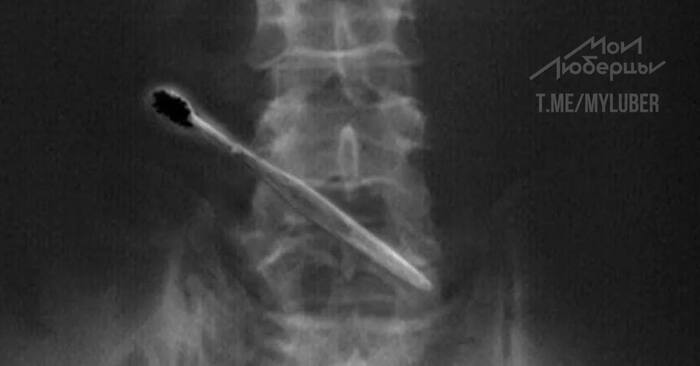

А кто-то, не может таблетку проглотить

Жительница Подмосковья случайно проглотила зубную щетку, пока чистила зубы.

16-летняя девушка пришла к врачам центра им. Рошаля с жалобами на тошноту и боль в верхней части груди. Девушку «просветили» и нашли у неё в желудке зубную щетку.

Пациентка вспомнила, что недавно чистила зубы, отвлеклась и зубная щетка куда-то пропала. Под общей анестезией и с помощью эндоскопического инструмента щетку достали за полчаса. Жизни девушки ничего не угрожает, её уже выписали под амбулаторное наблюдение.